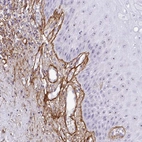

Immunohistochemical staining of human oral mucosa shows moderate nuclear positivity in squamous epithelial cells and distinct staining in vascular smooth muscle and basement membrane.